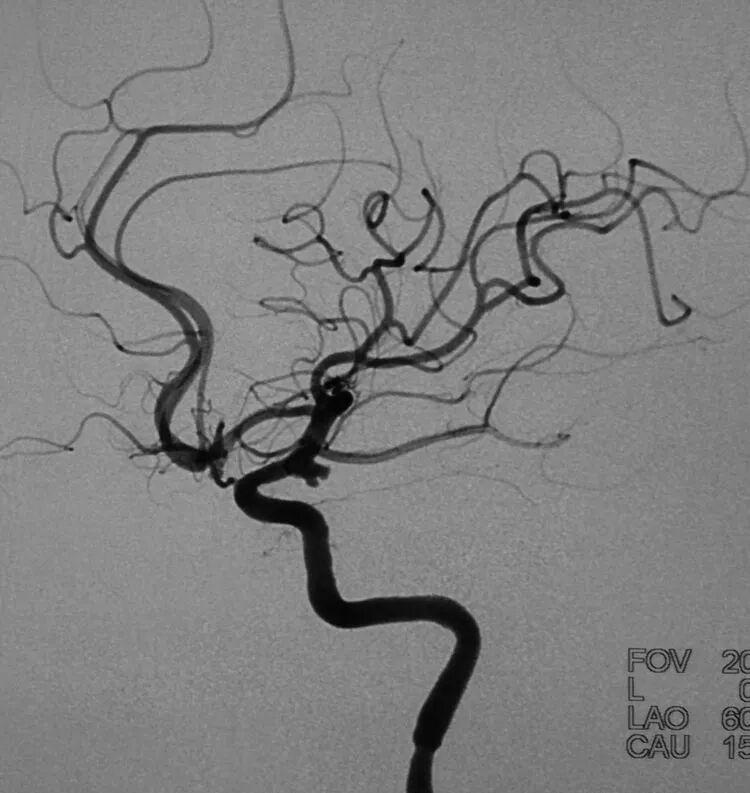

基底动脉顶端微小动脉瘤,是个有欺骗性的病例。从下面这个角度的造影看,瘤体长轴跟基底动脉主干平行,似乎用直头微导管栓塞即可

但从侧位造影和CTA观察,其实瘤体长轴还是跟基底动脉主干有成角的。这家医院的DSA机器没有三维重建工作站,只能参考CTA

于是我们把微导管头塑成S形

顺利完成该动脉瘤的栓塞。所以,要多角度观察动脉瘤跟载瘤动脉的解剖走行,即使硬件上没有三维工作站,咱们头脑中也要有立体构象,不要一叶障目,被狡猾的敌人所欺骗